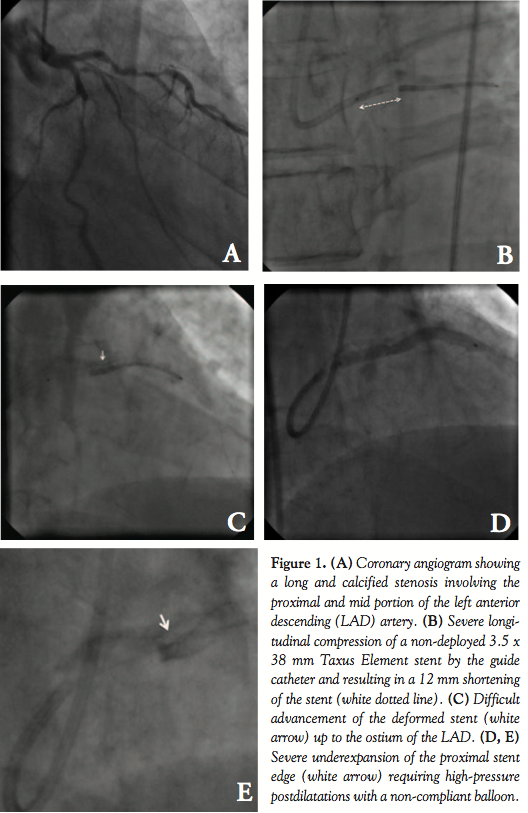

Case Report. A 59-year-old man was admitted for elective percutaneous coronary intervention (PCI) of a long and calcified stenosis involving the proximal and mid portion of the left anterior descending artery (LAD; Figure 1A). An ATW wire (Cordis Corporation) and a Whisper wire (Abbott Vascular) were placed in the distal LAD and the second diagonal branch, respectively, for side-branch protection as part of a provisional stenting approach. After predilatation with a 3 and 3.5 mm scoring compliant balloon (OrbusNeich), it was planned to cover the full lesion with a 3.5 x 38 mm Taxus Element stent (Boston Scientific). A first attempt to pass the lesion with the stent failed. On withdrawal of the crimped stent, the guide catheter was pulled in and engaged the distal left main (LM). Concomitantly, the proximal edge of the stent was blocked at the distal tip of the guide catheter. After several attempts to pull the crimped stent into the guide catheter, it became angiographically evident that the proximal edge of the stent had been longitudinally crushed while the supporting balloon had partially entered the guide catheter (Figure 1B). As a result, the stent was shortened in

length by approximately 12 mm before deployment (Figure 1B). Due to this major proximal stent deformation, the operator failed to recapture the stent into the guide catheter. Subsequently, it became difficult to advance the balloon with the compressed stent from the LM into the LAD. After careful manipulation, the proximal edge of the stent could be placed at the ostium of the LAD, but the distal part of the lesion was not covered (Figures 1C and 1D). After stent deployment, the angiography showed a concentrated mass of unapposed struts at the proximal edge of the stent (Figure 1E). Postdilatation was performed at high pressure with a 3.5 mm non-compliant balloon and a 3 x 12 mm Taxus Element stent was placed on the residual LAD lesion. The final angiographic result was deemed acceptable (Figure 1F) and the patient remained well throughout the 8-month clinical follow-up.